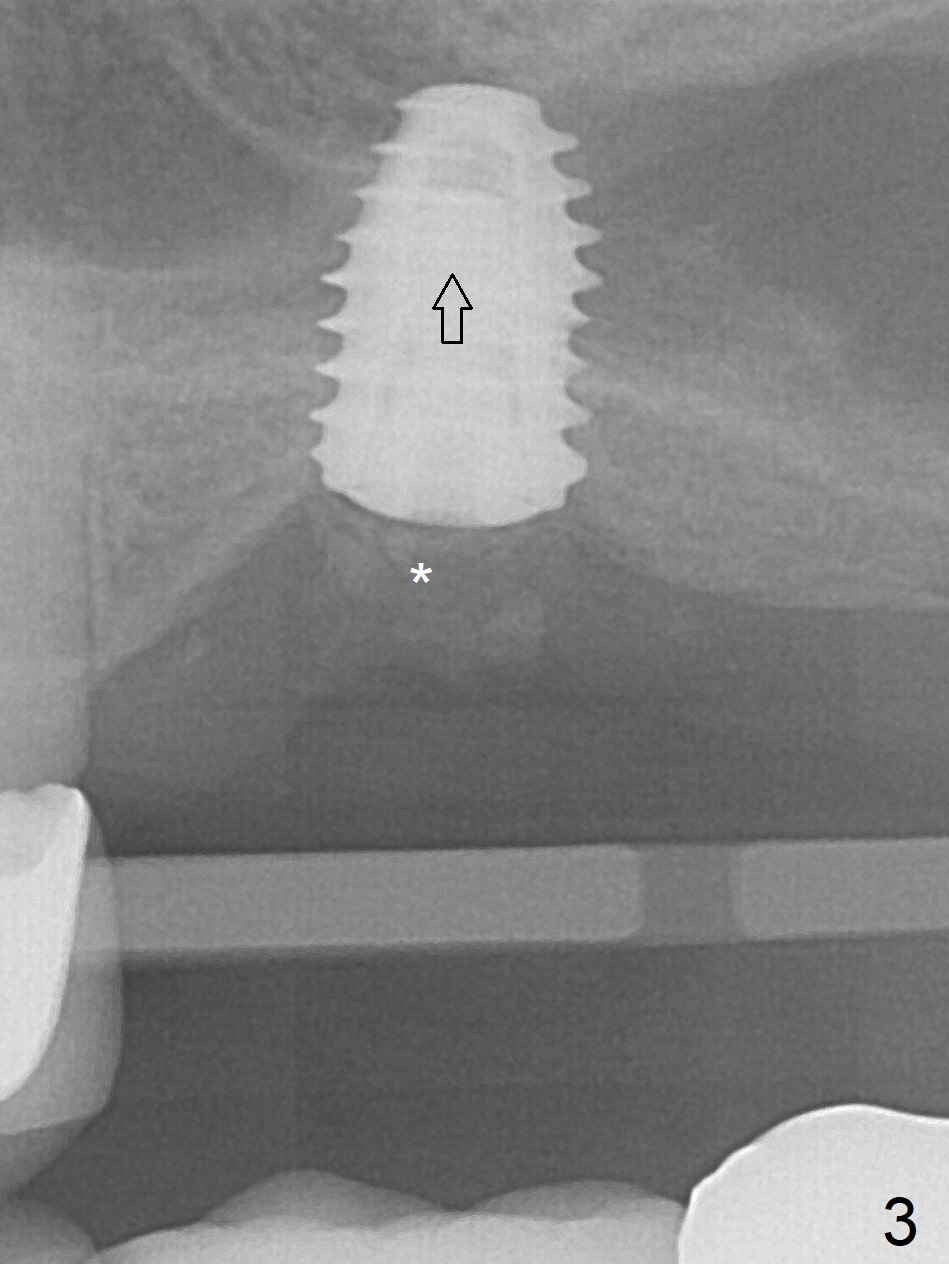

When the non-osteointegrated implant is removed, the sinus membrane is found to have been perforated. There is a history of clear discharge immediately postop ~ 1 year ago. Against the common wisdom, a 5x10 mm dummy implant is inserted with intention to correct the trajectory and 50 Ncm (Fig.1). With placement of Osteogen plug (presumably for repair of the perforation) and limited amount of Vanilla at the osteotomy, a 5x7.3 mm IS implant with SLA surface treatment is placed (Fig.2, ~ 40 Ncm). When the implant is further seated (Fig.3 arrow with bone graft coronally *)), its trajectory is within the normal limit (Fig.4 blue line). If the implant fails again, it must be due to the mild sinus infection. Bone graft, or preferably Osteogen Plug (collagen with osteoconductive ability) should have been done first. Mild tenderness exists with use of Water Pik 7 months post 2nd placement (Fig.5). Uncover shows that the implant is stable. A 6x3 mm healing abutment is placed. Next appointment a temporary crown will be fabricated for progressive loading. The abutment screw needs retightening 8 months post cementation, probably related to poor crown/implant ratio and missing 2nd molar (Fig.6).